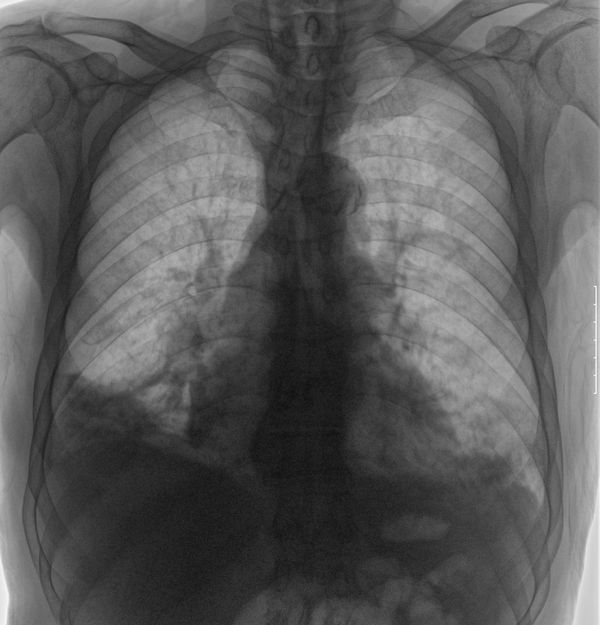

标题: X6625:m78,胸疼月余,咯血3天, [打印本页]

两下肺片状密度不均增高影,边缘不清,两侧膈面不清,右侧肋膈角消失。主动脉弧形钙化影。考虑两下肺感染性病变。抗炎后复查或ct检查。

两下肺感染;右侧胸腔积液,主动脉硬化;可疑肺血增多;建议ct检查了解详细情况

不知心肾功能怎样,肺水肿不能除外。

右侧胸膜属于陈旧性病变,左下肺野属支扩病变,慢支肺气肿合并肺部感染。

考虑支扩合并两下肺感染性病变,右侧胸腔积液局部包裹。建议ct明确。